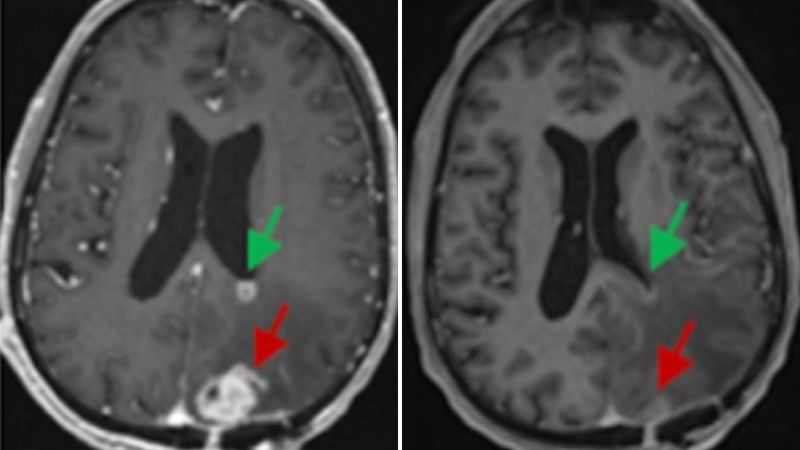

Researchers have developed a noninvasive nasal nanotherapy using gold-based spherical nucleic acids that successfully eradicated glioblastoma tumors in mice by activating immune pathways, offering a promising new approach for treating deadly brain cancers.